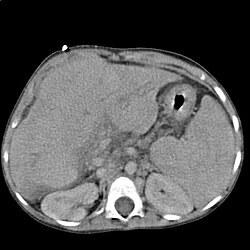

Ciroza jetre je kronična bolest jetre tijekom koje se jetreno tkivo zamjenjuje vezivnim tkivom što za krajnju posljedicu ima prestanak funkcija jetre.